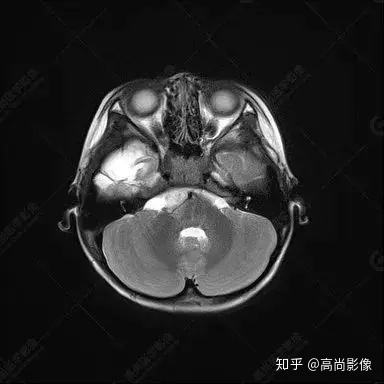

右側(cè)顳葉腫瘤切除術(shù)后(具體不詳):右側(cè)顳部骨質(zhì)不連續(xù)呈術(shù)后改變,右側(cè)顳葉術(shù)區(qū)見片狀長T1長T2信號(hào)影,F(xiàn)LAIR呈低信號(hào);術(shù)區(qū)后方右側(cè)顳枕葉見一巨大占位性病變影,邊界欠清,大小約6.2×5.8×4.3cm(前后×左右×上下),信號(hào)不均勻,T1WI呈等稍低信號(hào)間雜少許高信號(hào),T2WI呈高稍低混雜信號(hào),DWI示部分病灶彌散受限,相應(yīng)ADC圖減低,磁敏感序列見部分呈極低信號(hào),增強(qiáng)掃描可見明顯不均勻強(qiáng)化,鄰近硬腦膜及小腦幕增厚并明顯強(qiáng)化;另延髓右前方及右側(cè)橋小腦角區(qū)見一不規(guī)則形異常信號(hào)影,大小約3.2×1.3×3.7cm(左右×前后×上下),呈長T1稍長T2信號(hào),F(xiàn)LAIR呈等信號(hào),DWI未見受限,增強(qiáng)后明顯均勻強(qiáng)化,鄰近腦膜明顯強(qiáng)化。鄰近腦實(shí)質(zhì)及右側(cè)顳角明顯受壓;左側(cè)大腦半球未見局灶性信號(hào)異常,中線結(jié)構(gòu)稍左移。

右側(cè)顳葉腫瘤切除術(shù)后:現(xiàn)術(shù)區(qū)后方右側(cè)顳枕葉及延髓右前方占位,右側(cè)顳枕部硬腦膜及小腦幕明顯強(qiáng)化,結(jié)合既往影像資料,考慮為胚胎源性惡性腫瘤,如非典型畸胎樣/橫紋肌樣瘤(AT/RT)或原始神經(jīng)外胚層腫瘤(PNET)。